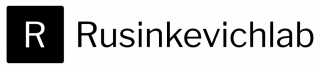

My research focuses on developing targeted cardiac drug-delivery strategies using the intrapericardial space as a novel and clinically relevant therapeutic access route. I established an intrapericardial catheter–based platform that enables direct, localized delivery of small molecules, biologics, nanoparticles, and cell-based therapies to the heart, allowing precise modulation of cardiac biology while minimizing systemic exposure.

This approach has gained rapid visibility following its initial publication, prompting multiple independent commentaries and underscoring strong interest from both clinical and basic research communities. Its early adoption highlights the platform’s novelty, translational potential, and relevance to cardiovascular therapeutics.

Building on this foundation, my work aims to expand this delivery system into a versatile preclinical pipeline for evaluating next-generation therapies targeting immune regulation, angiogenesis, fibrotic remodeling, ischemia/reperfusion injury, and pericardial inflammation in cardiovascular disease.